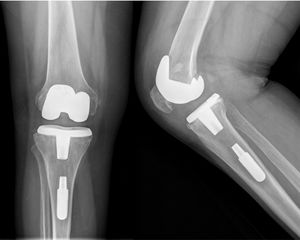

Se detectaron 5 casos (4,6%) de complicaciones intraoperatorias: una rotura accidental del ligamento colateral lateral, una fractura de la meseta tibial, una fractura de la tuberosidad tibial anterior y dos casos en que no fue posible atornillar adecuadamente el tornillo al polietileno, dejando el vástago dentro del canal sin conexión a la prótesis (fig. 1).

En 17 rodillas (15,7%), se detectó una deformidad preoperatoria en varo con un ángulo tibiofemoral medio de 2,7° (DE: 1,1) y en 87 rodillas (80,6%) una deformidad preoperatoria en valgo con un ángulo tibiofemoral medio de 15,1° (DE: 5,3). Las 4 rodillas restantes fueron neutras (5-7° de ángulo tibiofemoral). La alineación tibiofemoral postoperatoria media fue de 6,8° (DE: 1,9). La distribución de los valores de los ángulos tibiofemorales antes de la ATR y en las radiografías realizadas al final del seguimiento, se muestra en la figura 2. Además, existieron líneas radiolucentes en 18 pacientes (16,7%), y se observó osteólisis en 16 pacientes (14,8%).